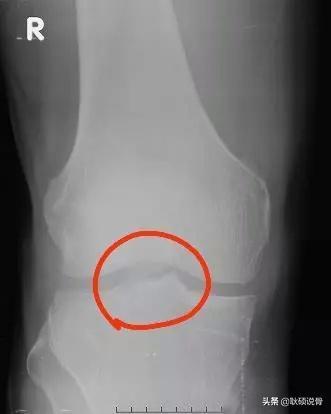

误区二、很多人看见自己的X线片时,都会发现下面这个结构:髁间嵴。这个误导性极强的结构被许多人认为是增生出来的骨刺。其实它只是胫骨的一个正常结构罢了,因为它特别锐利所以叫做“嵴”。